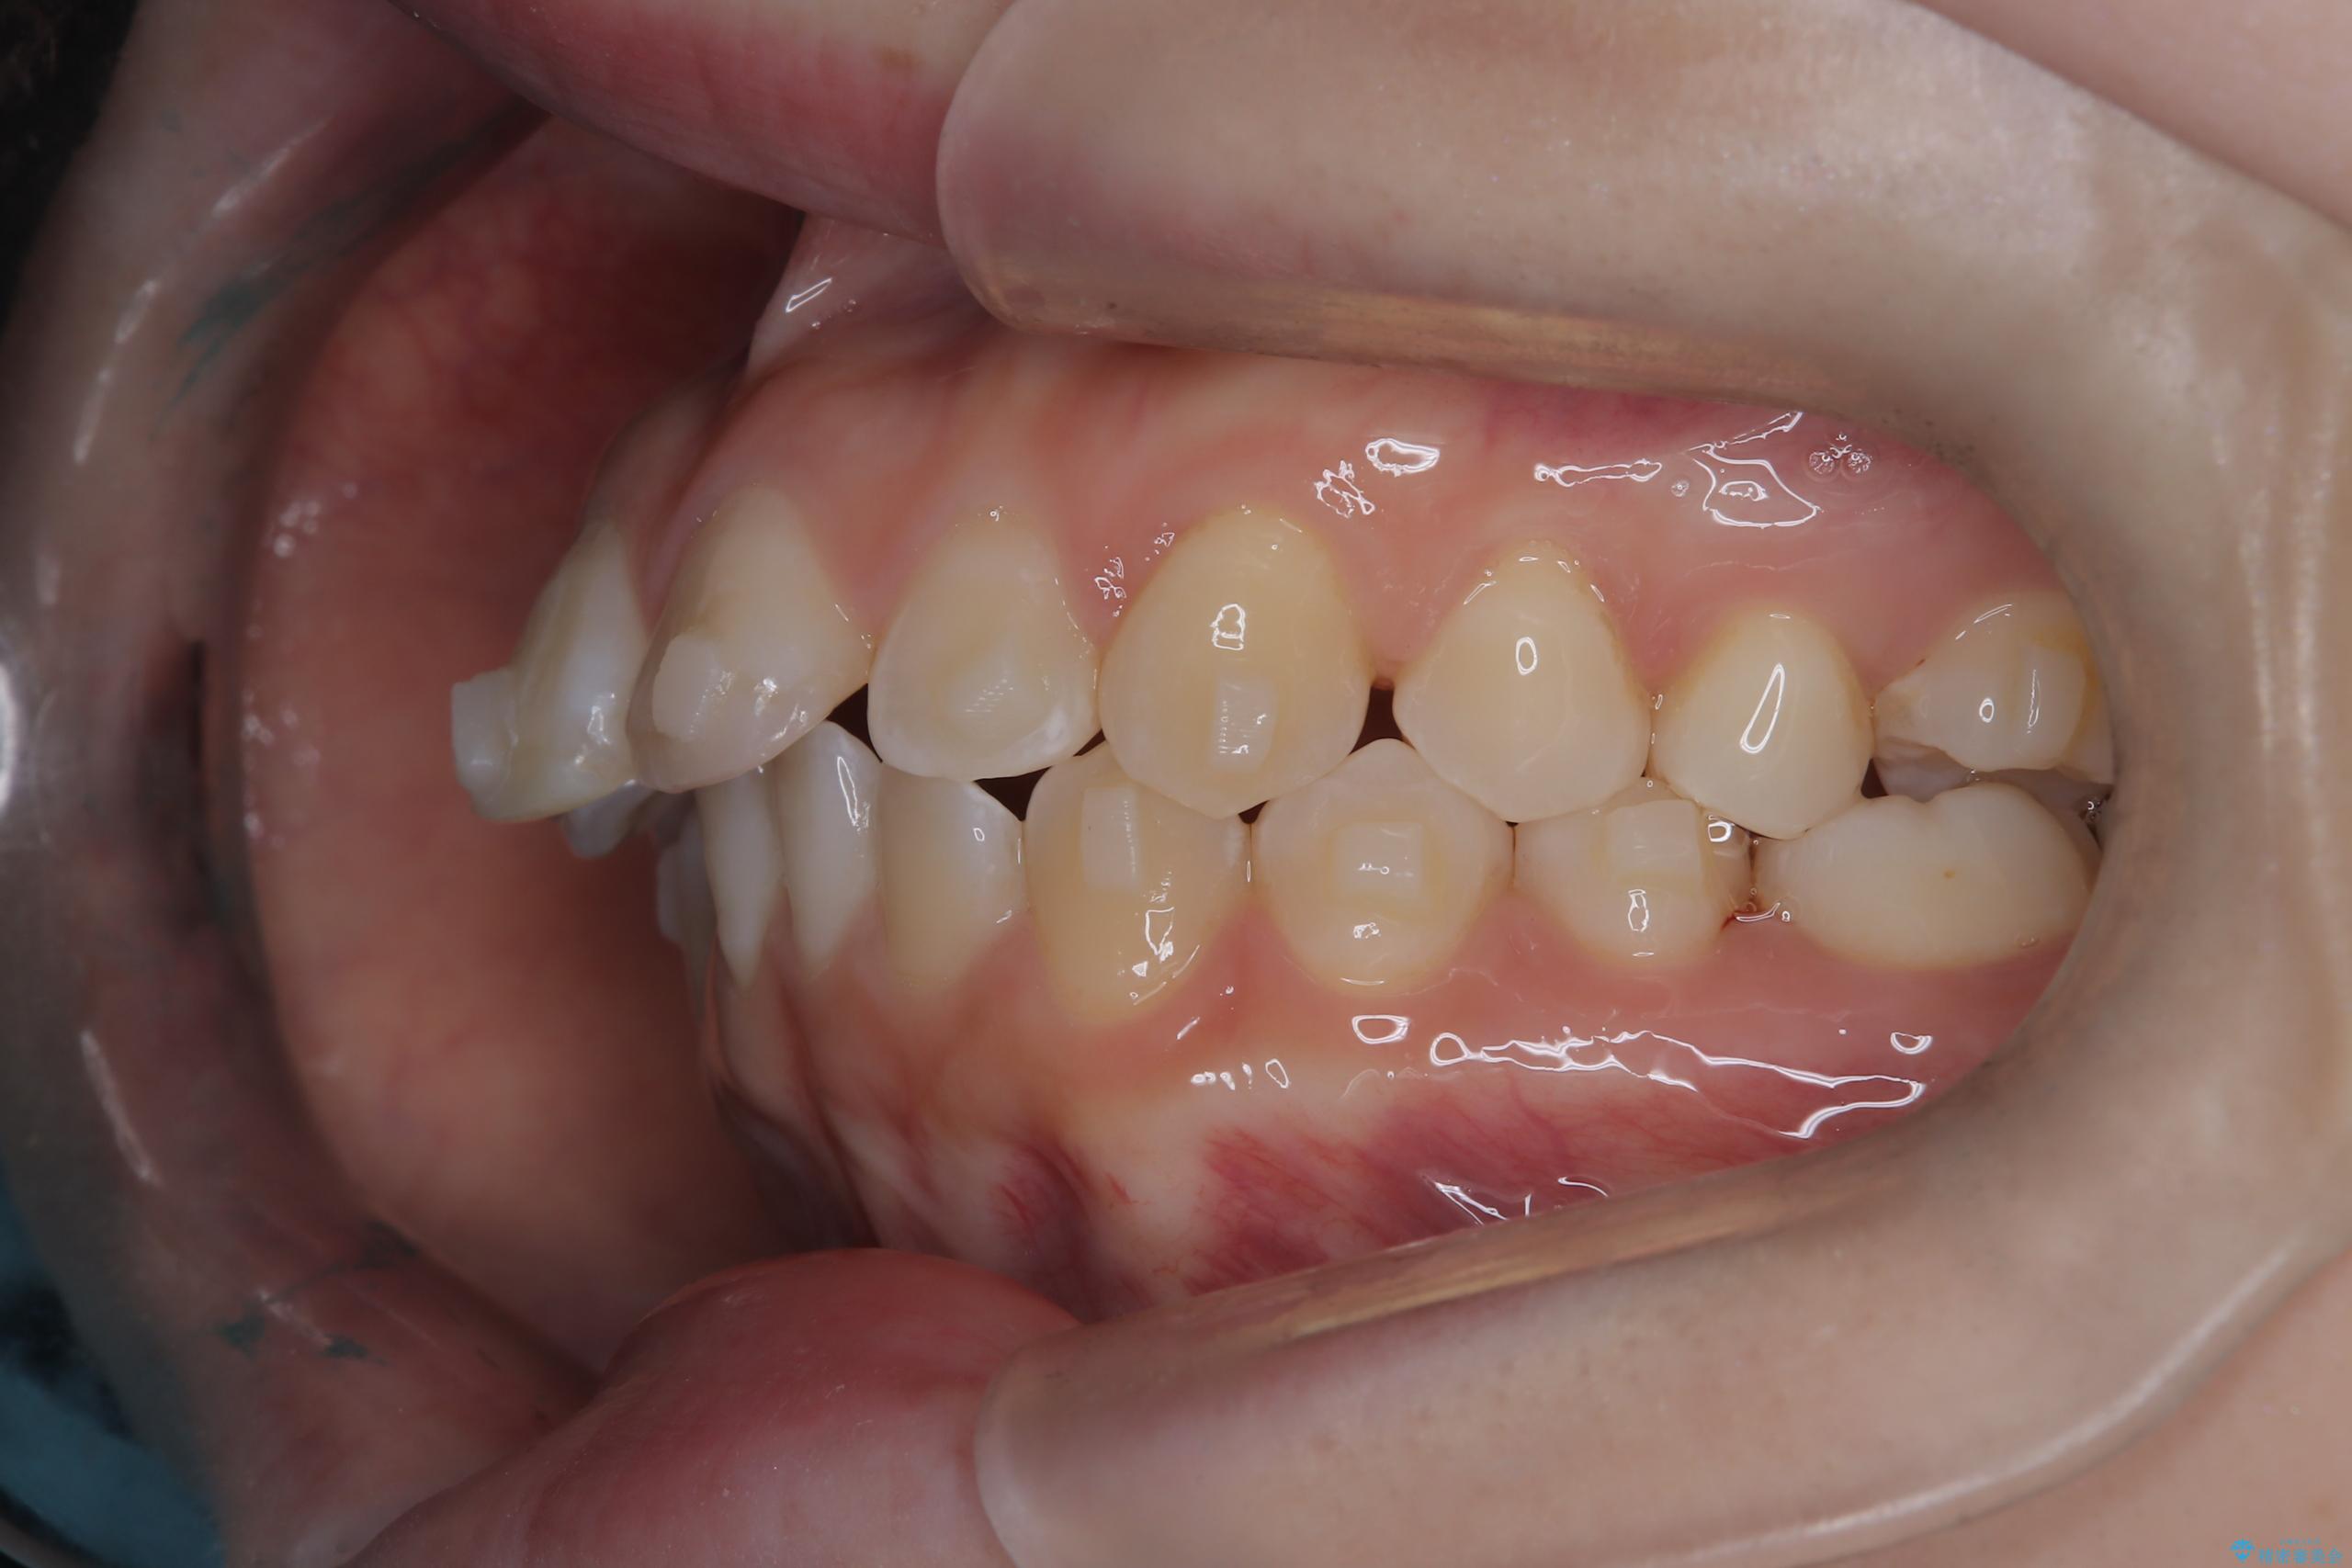

- 前歯のデコボコ(叢生)を気にされてご来院されました。精密な検査の結果、歯が並ぶスペースが不足していることが判明。患者様のご希望から、透明で目立ちにくいインビザライン(マウスピース矯正)による治療計画を立案しました。抜歯を避け、奥歯全体を奥へ動かす遠心移動という方法でスペースを確保し、前歯の叢生を解消することを目指します。

今回の矯正治療では、透明なマウスピース型の装置インビザラインを使用しました。この装置は取り外し可能で、日常生活で目立ちません。治療は、緻密に計算された計画に基づき、段階的に作製されたマウスピースを交換していくことで、奥歯から順に全体を後方へ移動させる遠心移動を実施。これにより、前歯を並べるための十分なスペースが確保され、デコボコが解消されました。抜歯することなく、機能的にも審美的にも整った美しい歯並びを獲得していただけました。